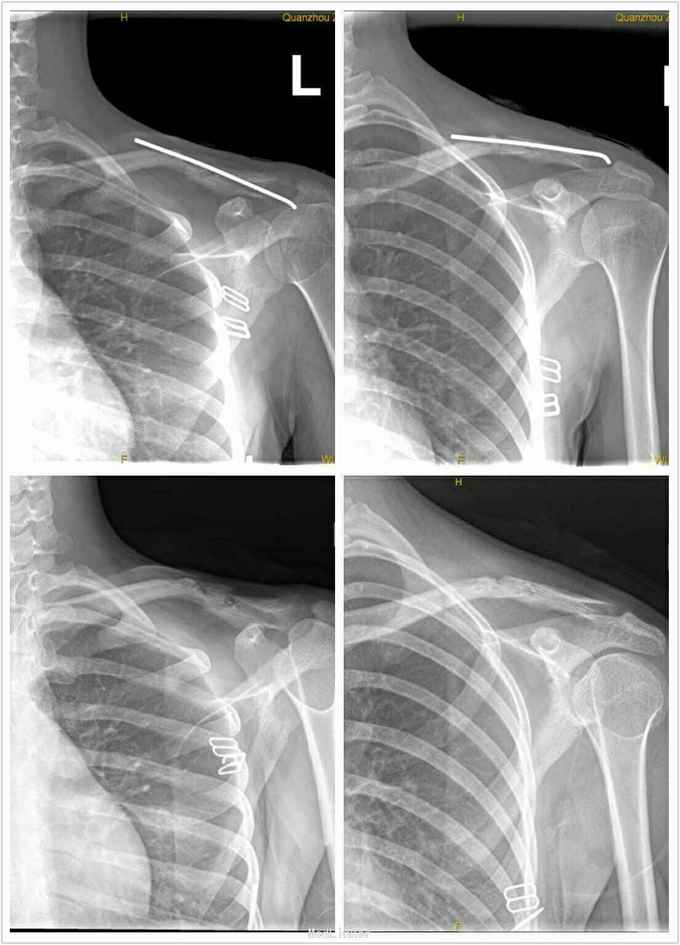

诊断: 左锁骨中外1/3骨折。 治疗:急诊在麻醉下行“左锁骨骨折闭合复位经皮克氏针内固定术”。

术后随访4个月,骨折愈合后行内固定物取出术。但该患者术后骨折端可见小片金属碎屑存留,术后一个月并发局部皮肤化脓破溃,定期换药仍未见好转,最后内固定取出术后自愈。